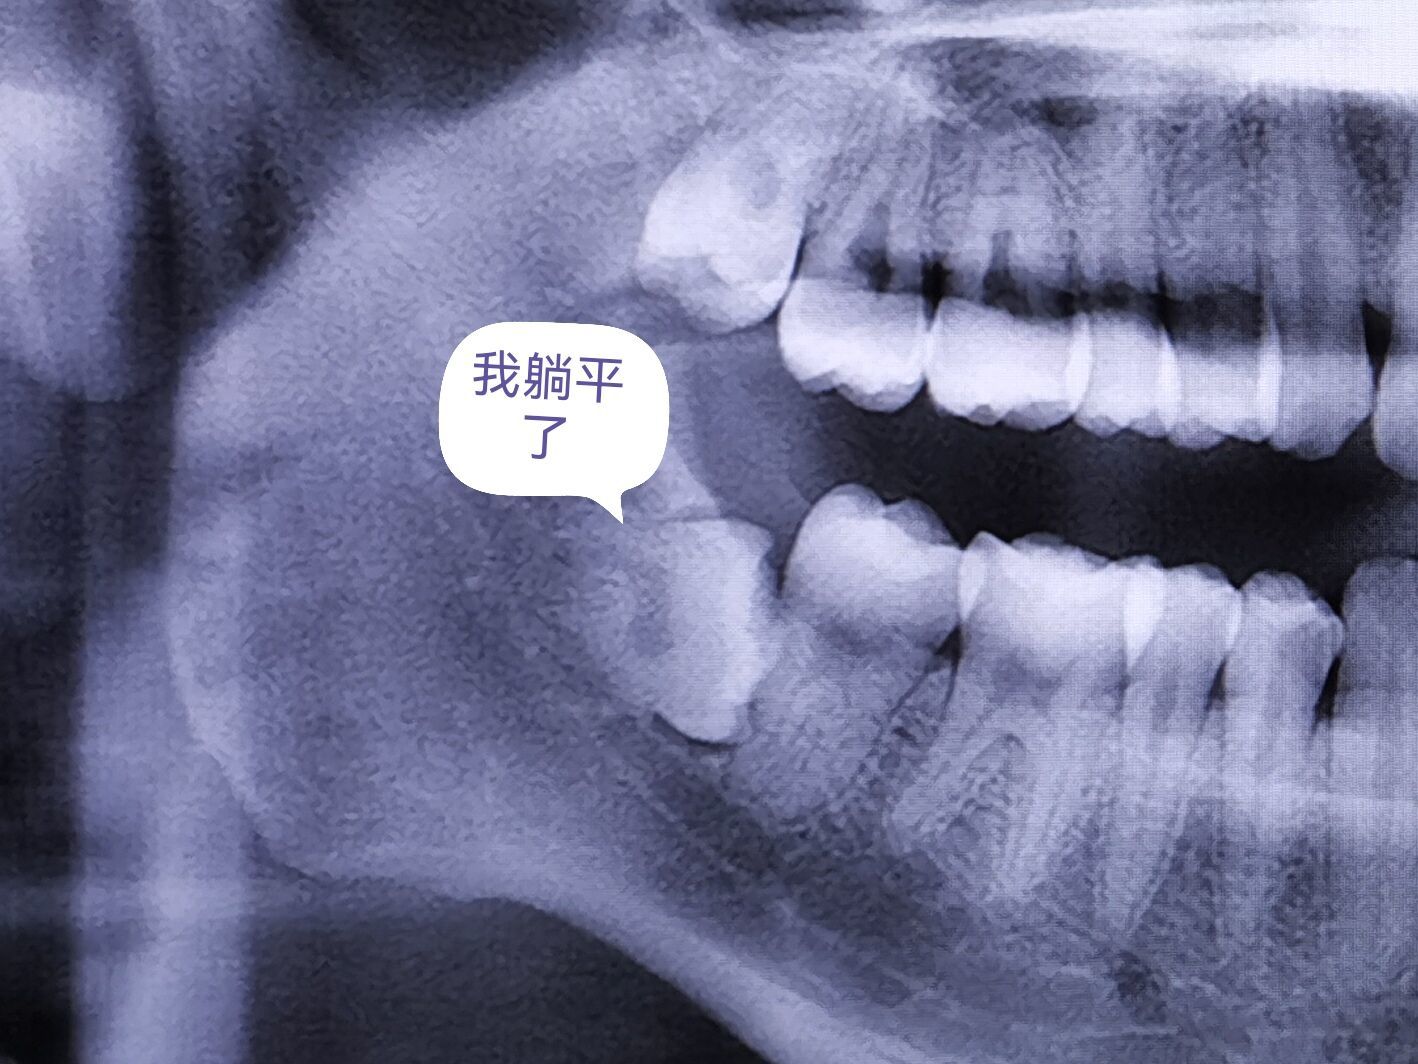

很明显,我并不是那种万中无一的天选智齿使用者,我甚至没法强行使用智齿...因为它们根本凑不出俩对,ct正面照看1号孤寡智齿好似正常,但实际情况是左右错位的,类似下图:

这种情况很容易因为牙齿错位造成清洁盲区,这种牙缝特别容易积攒食物残渣,积累食物残渣久了又会导致口臭、蛀牙等等。所以医生给我的建议是拔除。至于我另外一边的更是重量级:

它直接在我的牙床里躺平了,还威胁着我正常健康的牙齿,万一它哪天想起来发展了,可能会导致我类似这样的“牙齿车祸”,一不小心口腔健康车毁人亡: